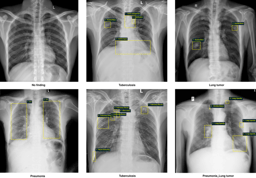

Several examples of pediatric CXR images with radiologists’ annotations. Local labels marked by radiologists are plotted on the original images. The global labels, that classify images into diseases, are in bold.

As you can see in the figure above, the local labels should be annotated with rectangle bounding boxes that localize the findings, while the global labels reflect the diagnostic impression of the radiologist at the image level. For algorithm development, we randomly divided the dataset into two parts: the training set of 7,728 scans (84.7%) and the test set of 1,397 scans (15.3%). To the best of our knowledge, the released PediCXR is currently the largest public pediatric CXR dataset with radiologist-generated annotations in both training and test sets. We believe the introduction of the PediCXR provides a suitable imaging source for investigating the ability of supervised machine learning models in identifying common lung diseases in pediatric patients. The dataset characteristics of PediCXR are shown below.